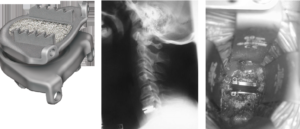

(Above left): MRI scan of the cervical spine showing a typical disc protrusion between the 5th and 6th cervical vertebra compressing the spinal cord

(Above middle): A Schematic diagram of a typical anterior discectomy and fusion procedure. A block of bone graft is placed into the space left when the disc is removed

(Above right): A postoperative x-ray on the patient shown to the left. The disc has been removed, a block of bone has fused the 5th and 6th vertebrae and a plate with screws holds it into place